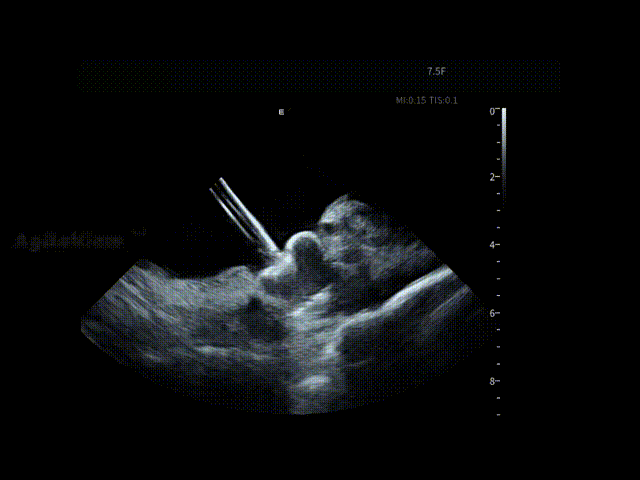

在完成房颤消融关键步骤后,邹操教授操作7.5Fr AgileView™ ICE导管进入左心房,该导管为四向180°打弯,可轻松进入左房,为后续左心耳评估与封堵操作提供无缝衔接的影像支持。

通过ICE的多角度实时成像,术者在左房内近距离观察左心耳的开口形态、分叶数结构及周围解剖关系,并对潜在血栓进行动态筛查,并选择合适的封堵器型号选择并制定释放策略。

AgileView™ 7.5Fr ICE的超细管径设计,使ICE在左房内多任务操作时“存在感更低”,在消融导管、封堵输送系统等多导管并行的情况下,仍能保持稳定、清晰的视野,避免频繁调整,显著提升一站式手术的流程顺畅性与可控性。手术结束前,术者再次使用ICE导管进行心包监测,确认无明显变化后,整体手术结束。

90°观察LAA

90°观察封堵器

90°送猪尾导丝进LAA

135°观察封堵器

135°释放封堵器

135°观察封堵器释放效果